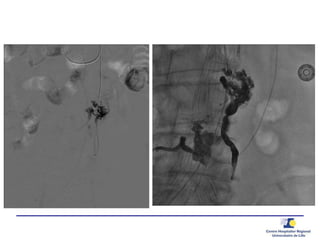

TYPE 2 – Quelle(s) artère(s) alimente(nt) le sac?

Inflow and Outflow

Inflow? Outflow?

outflow

inflow